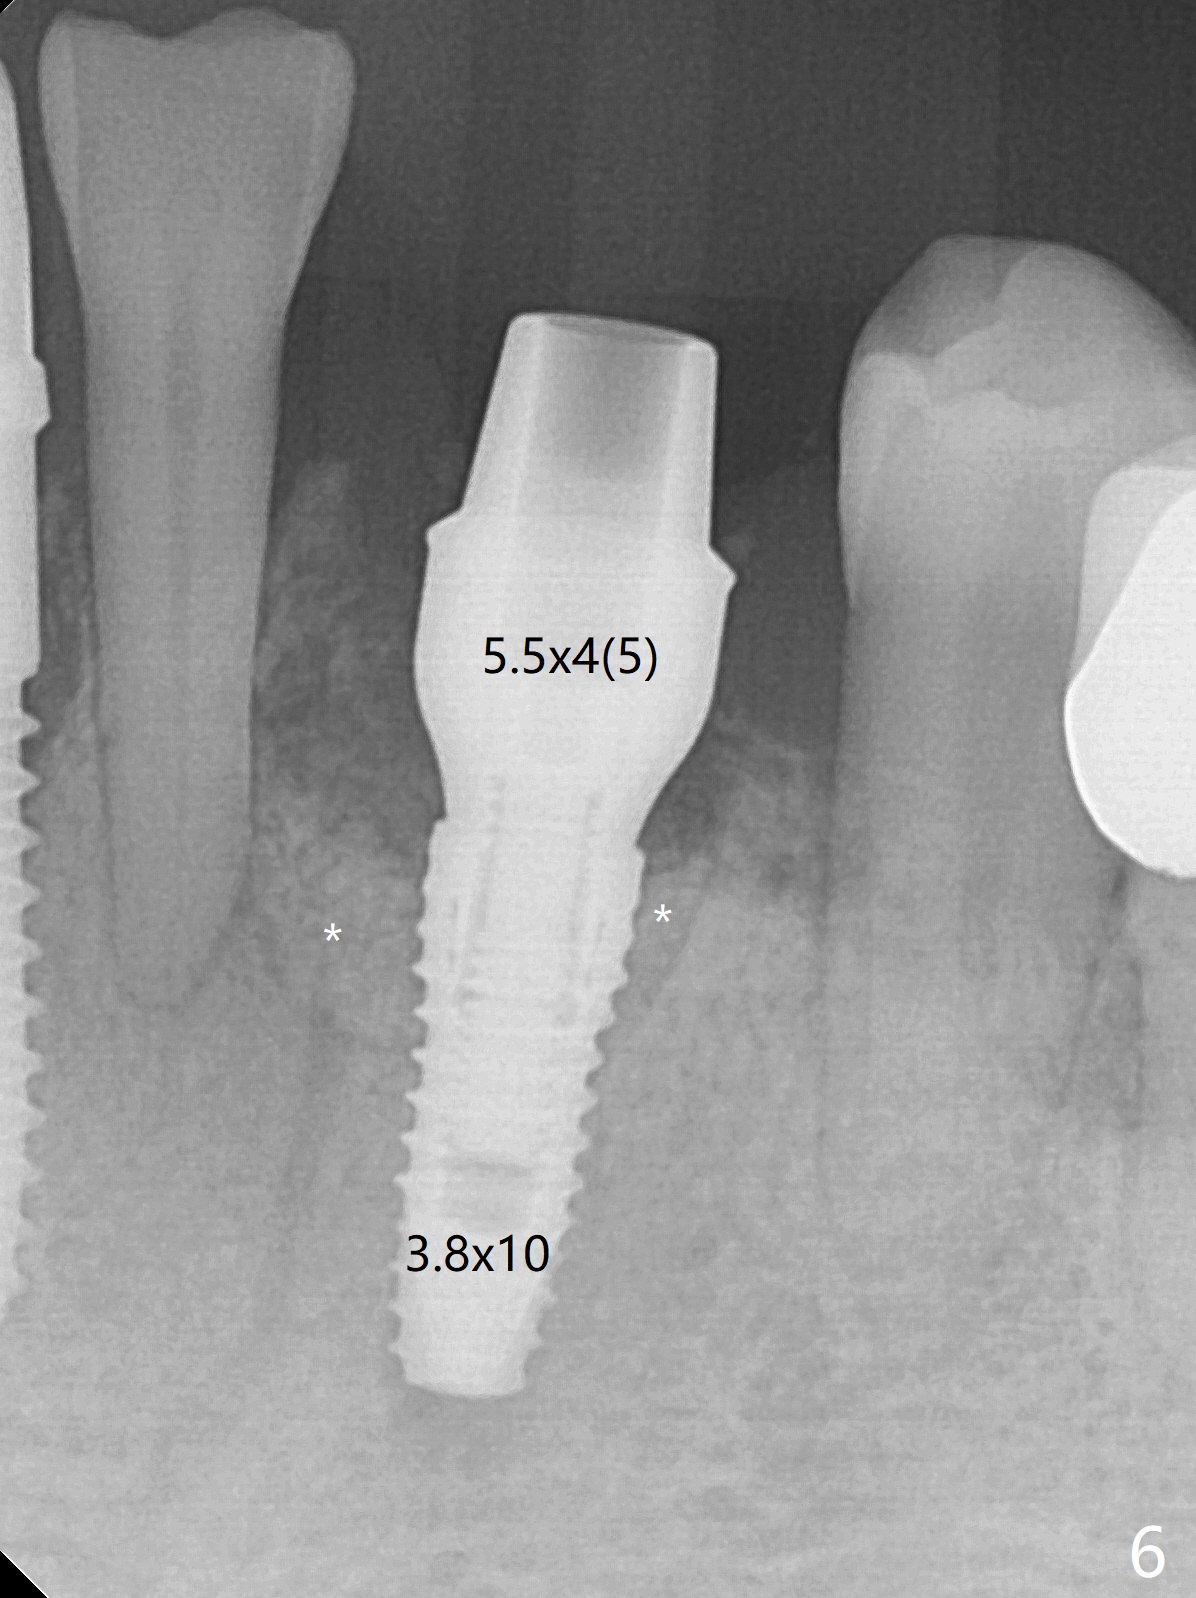

There is a fistula buccal to the apex of the tooth #23 preoperatively (Fig.1), which is related to loss of the buccal plate of the socket of #23. Therefore an implant is placed mainly in the socket of #22 (Fig.3). The lingual (Fig.2 L) gingiva appears to have more extensive inflammation. After extraction, the lingual (Fig.3 L) gingival margin is significantly lower than the buccal one. The lingual crest is ~ 4 mm lower than the buccal one. A 3.8x10 mm dummy implant is placed tentatively with an apical space (Fig.4). When a same dimension definitive implant is placed with 40 Ncm, it is 2 mm below the lingual gingival margin, whereas 6-7 mm below the buccal one (Fig.5). Vanilla graft is placed before placement of a 5.5x4(5) mm abutment (Fig.6,7). There is a 2-3 mm lingual (L) gap to be filled with the allograft secondarily to prevent periimplantitis (Fig.7). Later the abutment is changed to a longer and smaller one (Fig.8) with more of the allograft (*). After trimming of the abutment (Fig.9 (*: papilla between the fused teeth)), an immediate provisional is fabricated to close the socket (Fig.10, similar to Fig.1). The majority of the bone graft seems to be in place 8 months postop (Fig.12). The implant appears to have been placed buccal, consistent with the thin and slightly erythematous buccal gingiva (Fig.13). The ridge completely regenerates 2 years post cementation (Fig.14).